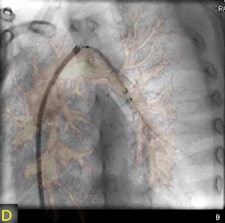

"The fusion of 3D reconstructions with live fluoroscopic images during catheterization may help to find the ideal fluoroscopic angulation during catheter-based interventions, to achieve difficult vascular crossings by the wire or the catheter, to choose the most appropriate material for catheterization, and to define and control optimized positioning of implants such as stents or valve prostheses," Glöckler and colleagues explained.

"One unique feature of FD-CT is the possibility of merging 3D reconstructions with the real-time fluoroscopic image," a potentially useful way to identify ideal C-arm angulations for achieving wire passage for atypical vascular crossings, and to optimally depict the implant position of coils, plugs, stents, and valves," Glöckler and colleagues wrote. "In fact, image fusion of 3D reconstructed FD-CT images with the live fluoroscopic image was frequently rated as 'very useful' (57.4%)."

As a new technology, FD-CT also offers 3D imaging during cardiac catheterization, a clear extension of available imaging techniques, and the technique could also be useful for the assessment of valve function and great vessel anatomy, the group reported.